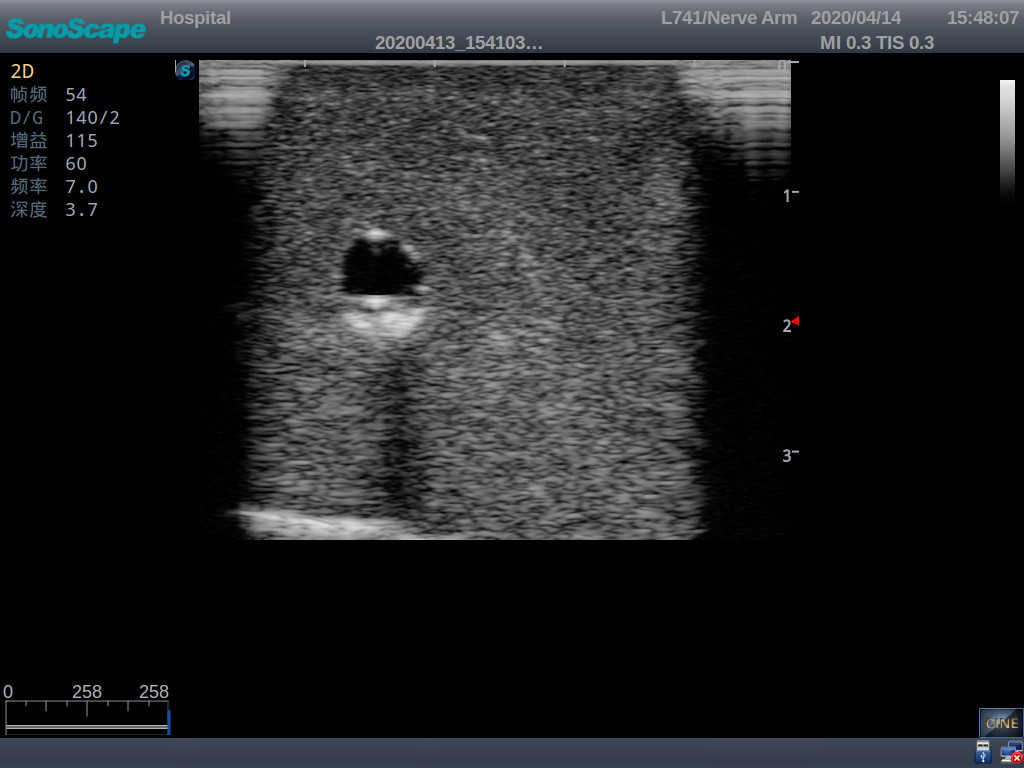

Model TYE1510.1

Product size(mm) 700×500×160

It is a model covering up from lobulus auriculae plane to the umbilical plane, and it has anatomical structures like clavicle, rib, sternocleidomastoid, jugular vein and basilic vein.

2)   It can be used by real ultrasound machines

3)   Clear and real images of the tissues and organs (basilic vein and superior vena cava)